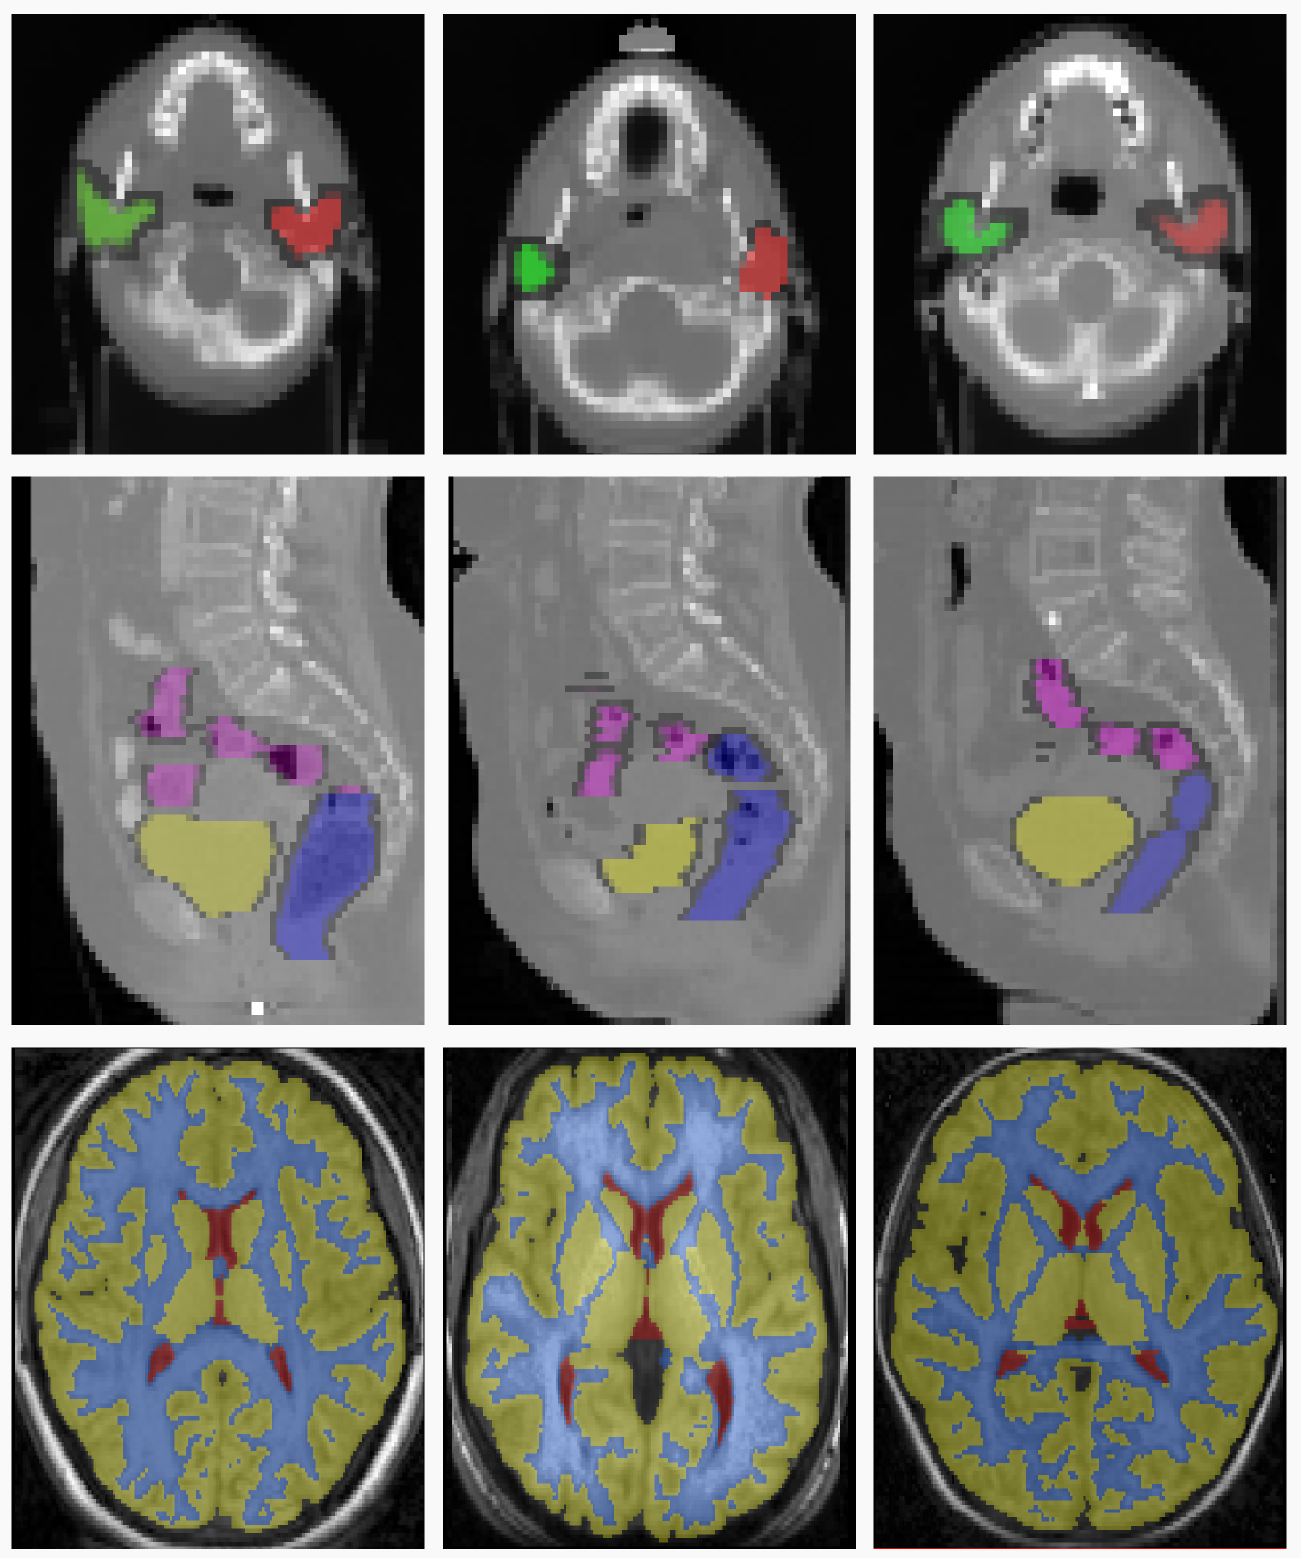

7 Qualitative results

Below we show visual results on three datasets used as a proof-of-concept for our proposed method, to highlight the effects of learning the weights of different metrics for the task of deformable registration.

Figure 3: Sample slices from three different volumes of the RT Parotids, RT Abdominal and IBSR datasets.The top row represents the sample slices from three different volumes of the RT Parotids dataset. The middle row represents the sample slices of the RT Abdominal dataset, and the last row represents the sample slices from the IBSR dataset.